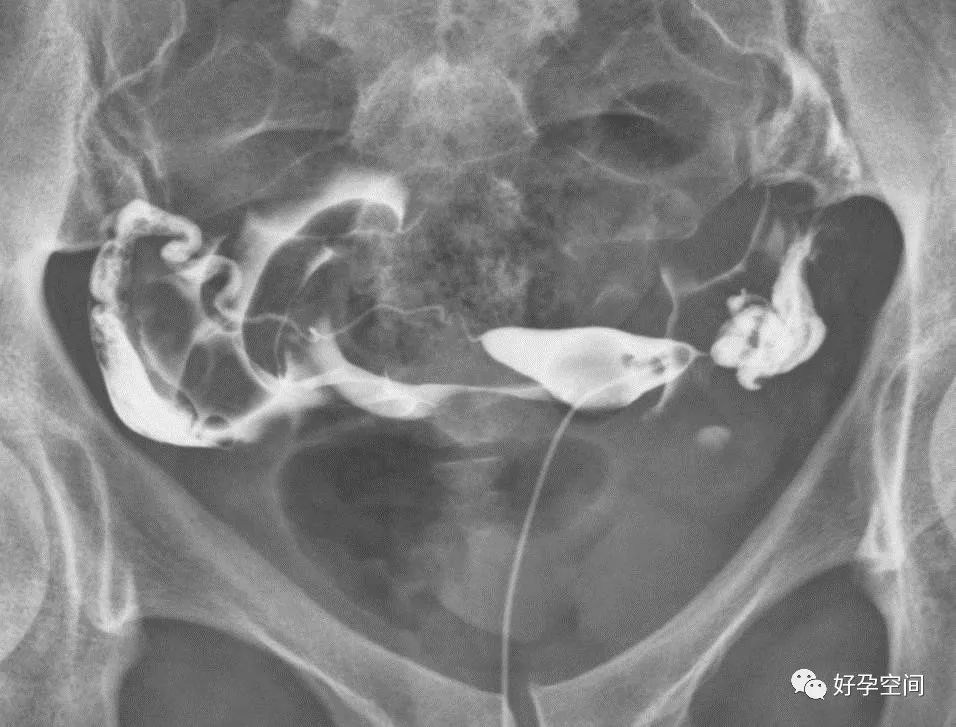

双侧输卵管下行